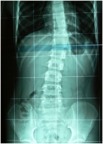

3_posture 3_posture_scanner

Exemple d’asymétrie posturale avec attitude scoliotique typique